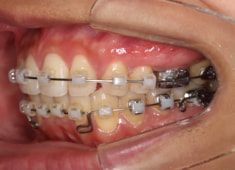

治療開始から24ヶ月後